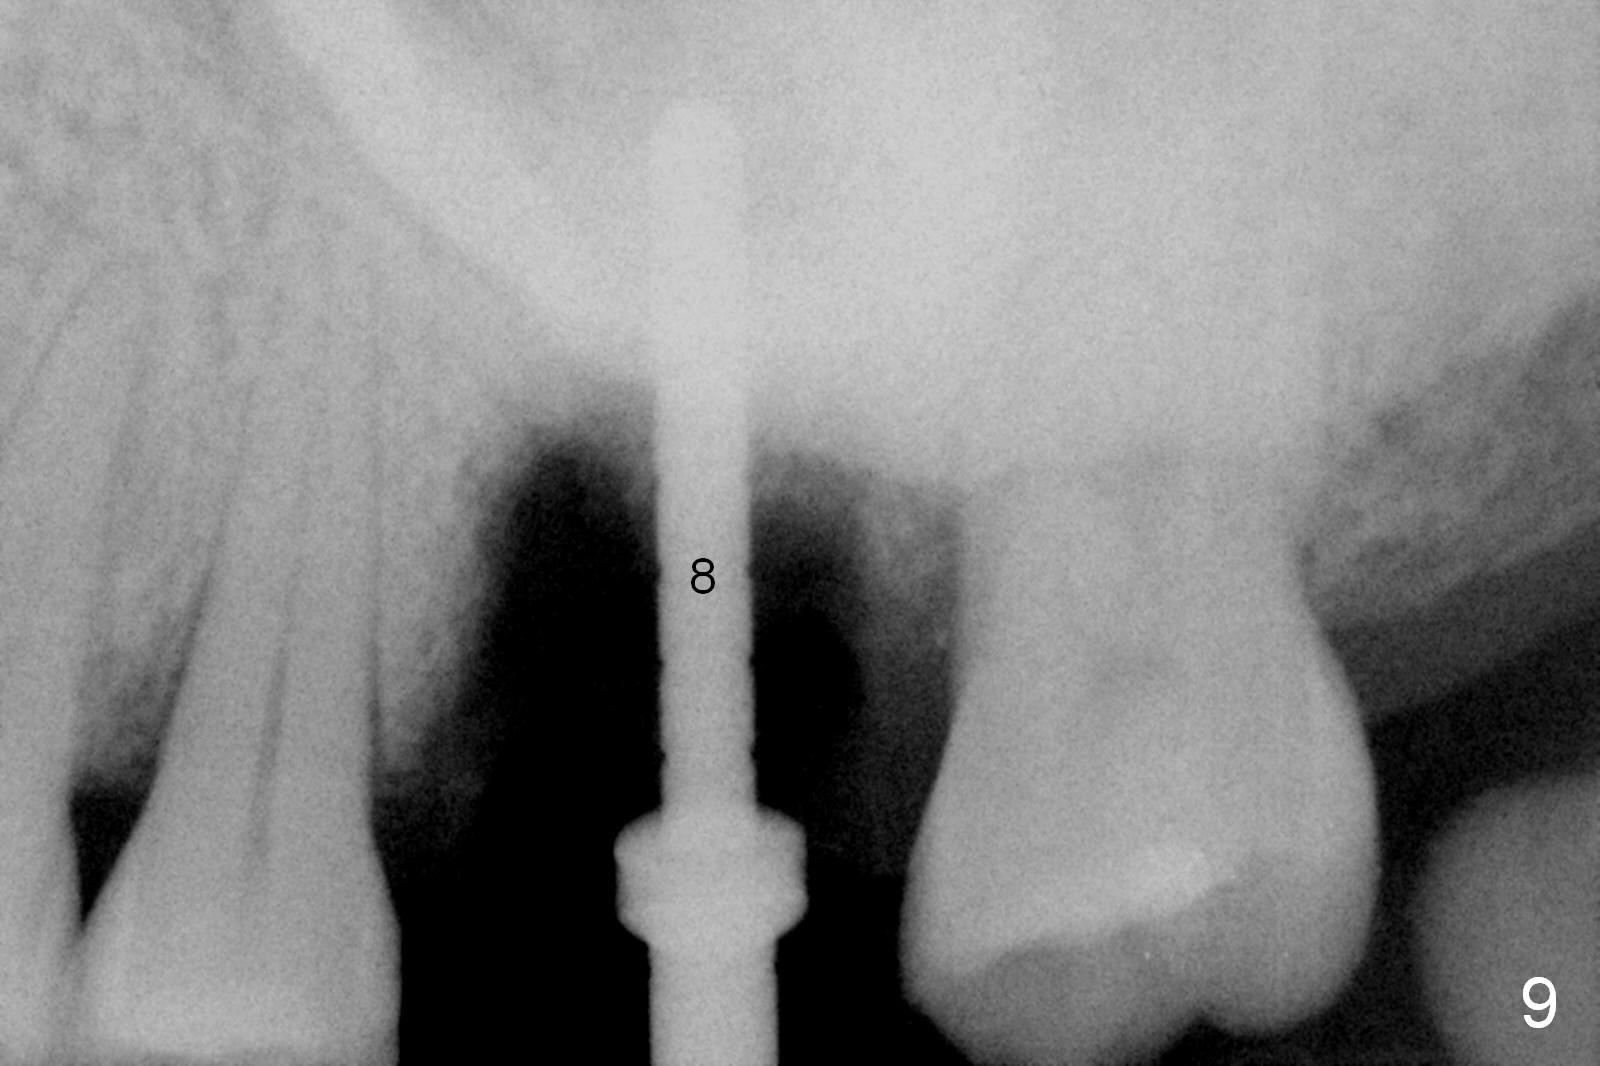

Osteotomy is initiated in the palatal slope of the septum 8 mm deep (Fig.8,9). A 5x11.5 mm implant is placed with insertion torque of 35 Ncm with ~ 2 mm sticking into the sinus with bone graft and 1.5-2.5 mm outside the septum. The latter is covered by bone graft (Fig.10 *). There is no nasal hemorrhage postop.

Oral hygiene is excellent postop. The socket heals around the abutment. Four months postop, the native bone appears to be approaching the implant surface (Fig.11 >).